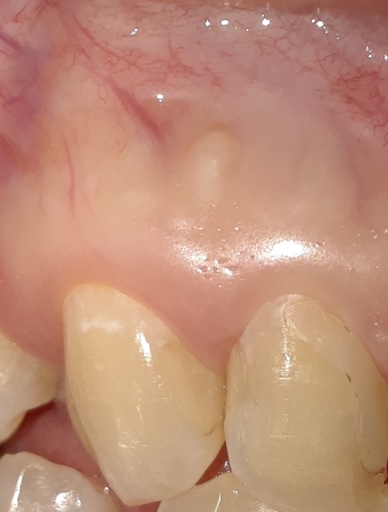

Root canal re-treatment- periapical cyst

Hi, I had a root canal re-treatment due to a periapical cyst. I had no symptoms but decided to be proactive. The doctor opened the canal and drained it. A week later the doctor disinfected the canal and filled it in. He didn't use calcium hydroxide at any time during the treatment. He explained that there was no need for it because the canal looked clean. It's been 7 months but I haven't checked the size of the cyst yet. Was the doctor correct in his decision or was the calcium hydroxide use necessary in my case? Thank you

Hi, I had a root canal re-treatment due to a periapical cyst. I had no symptoms but decided to be proactive. The doctor opened the canal and drained it. A week later the doctor disinfected the canal and filled it in. He didn't use calcium hydroxide...